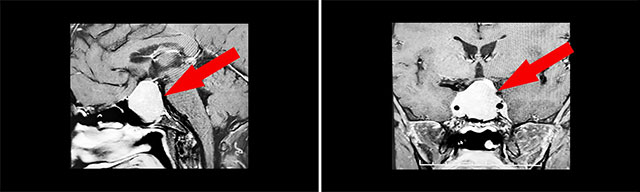

經(jīng)檢查發(fā)現(xiàn):鞍區(qū)MRI平掃+增強顯示:蝶鞍顯著擴大,鞍底下陷,骨質(zhì)變薄;其內(nèi)見球形團塊狀異常信號影,矢橫高徑約36×28×31mm,邊緣尚青晰、輪廓久光整,向上凸入鞍上池,視交叉受壓上抬;雙側(cè)海綿竇受累;垂體柄受壓、縮短、左側(cè)偏移。

腫瘤侵襲生長,包繞頸內(nèi)動脈,knosp分級IV級

▲ 腫瘤侵襲生長,包繞頸內(nèi)動脈,knosp分級IV級

針對該患者,唯一的治療方式就是手術(shù)切除腫瘤,減除腫瘤壓迫,以期盡早盡力使視力視野恢復(fù)。目前手術(shù)方式,主要有開顱手術(shù)切除腫瘤和經(jīng)單鼻孔-蝶竇入路切除腫瘤,而患者腫瘤如乒乓球大小,屬于垂體大腺瘤,并且侵襲生長,向兩側(cè)完全包繞左側(cè)頸內(nèi)動脈,knosp分級IV級,向上已突破鞍隔壓迫視神經(jīng)、視交叉、下丘腦;向下侵蝕充滿蝶竇。